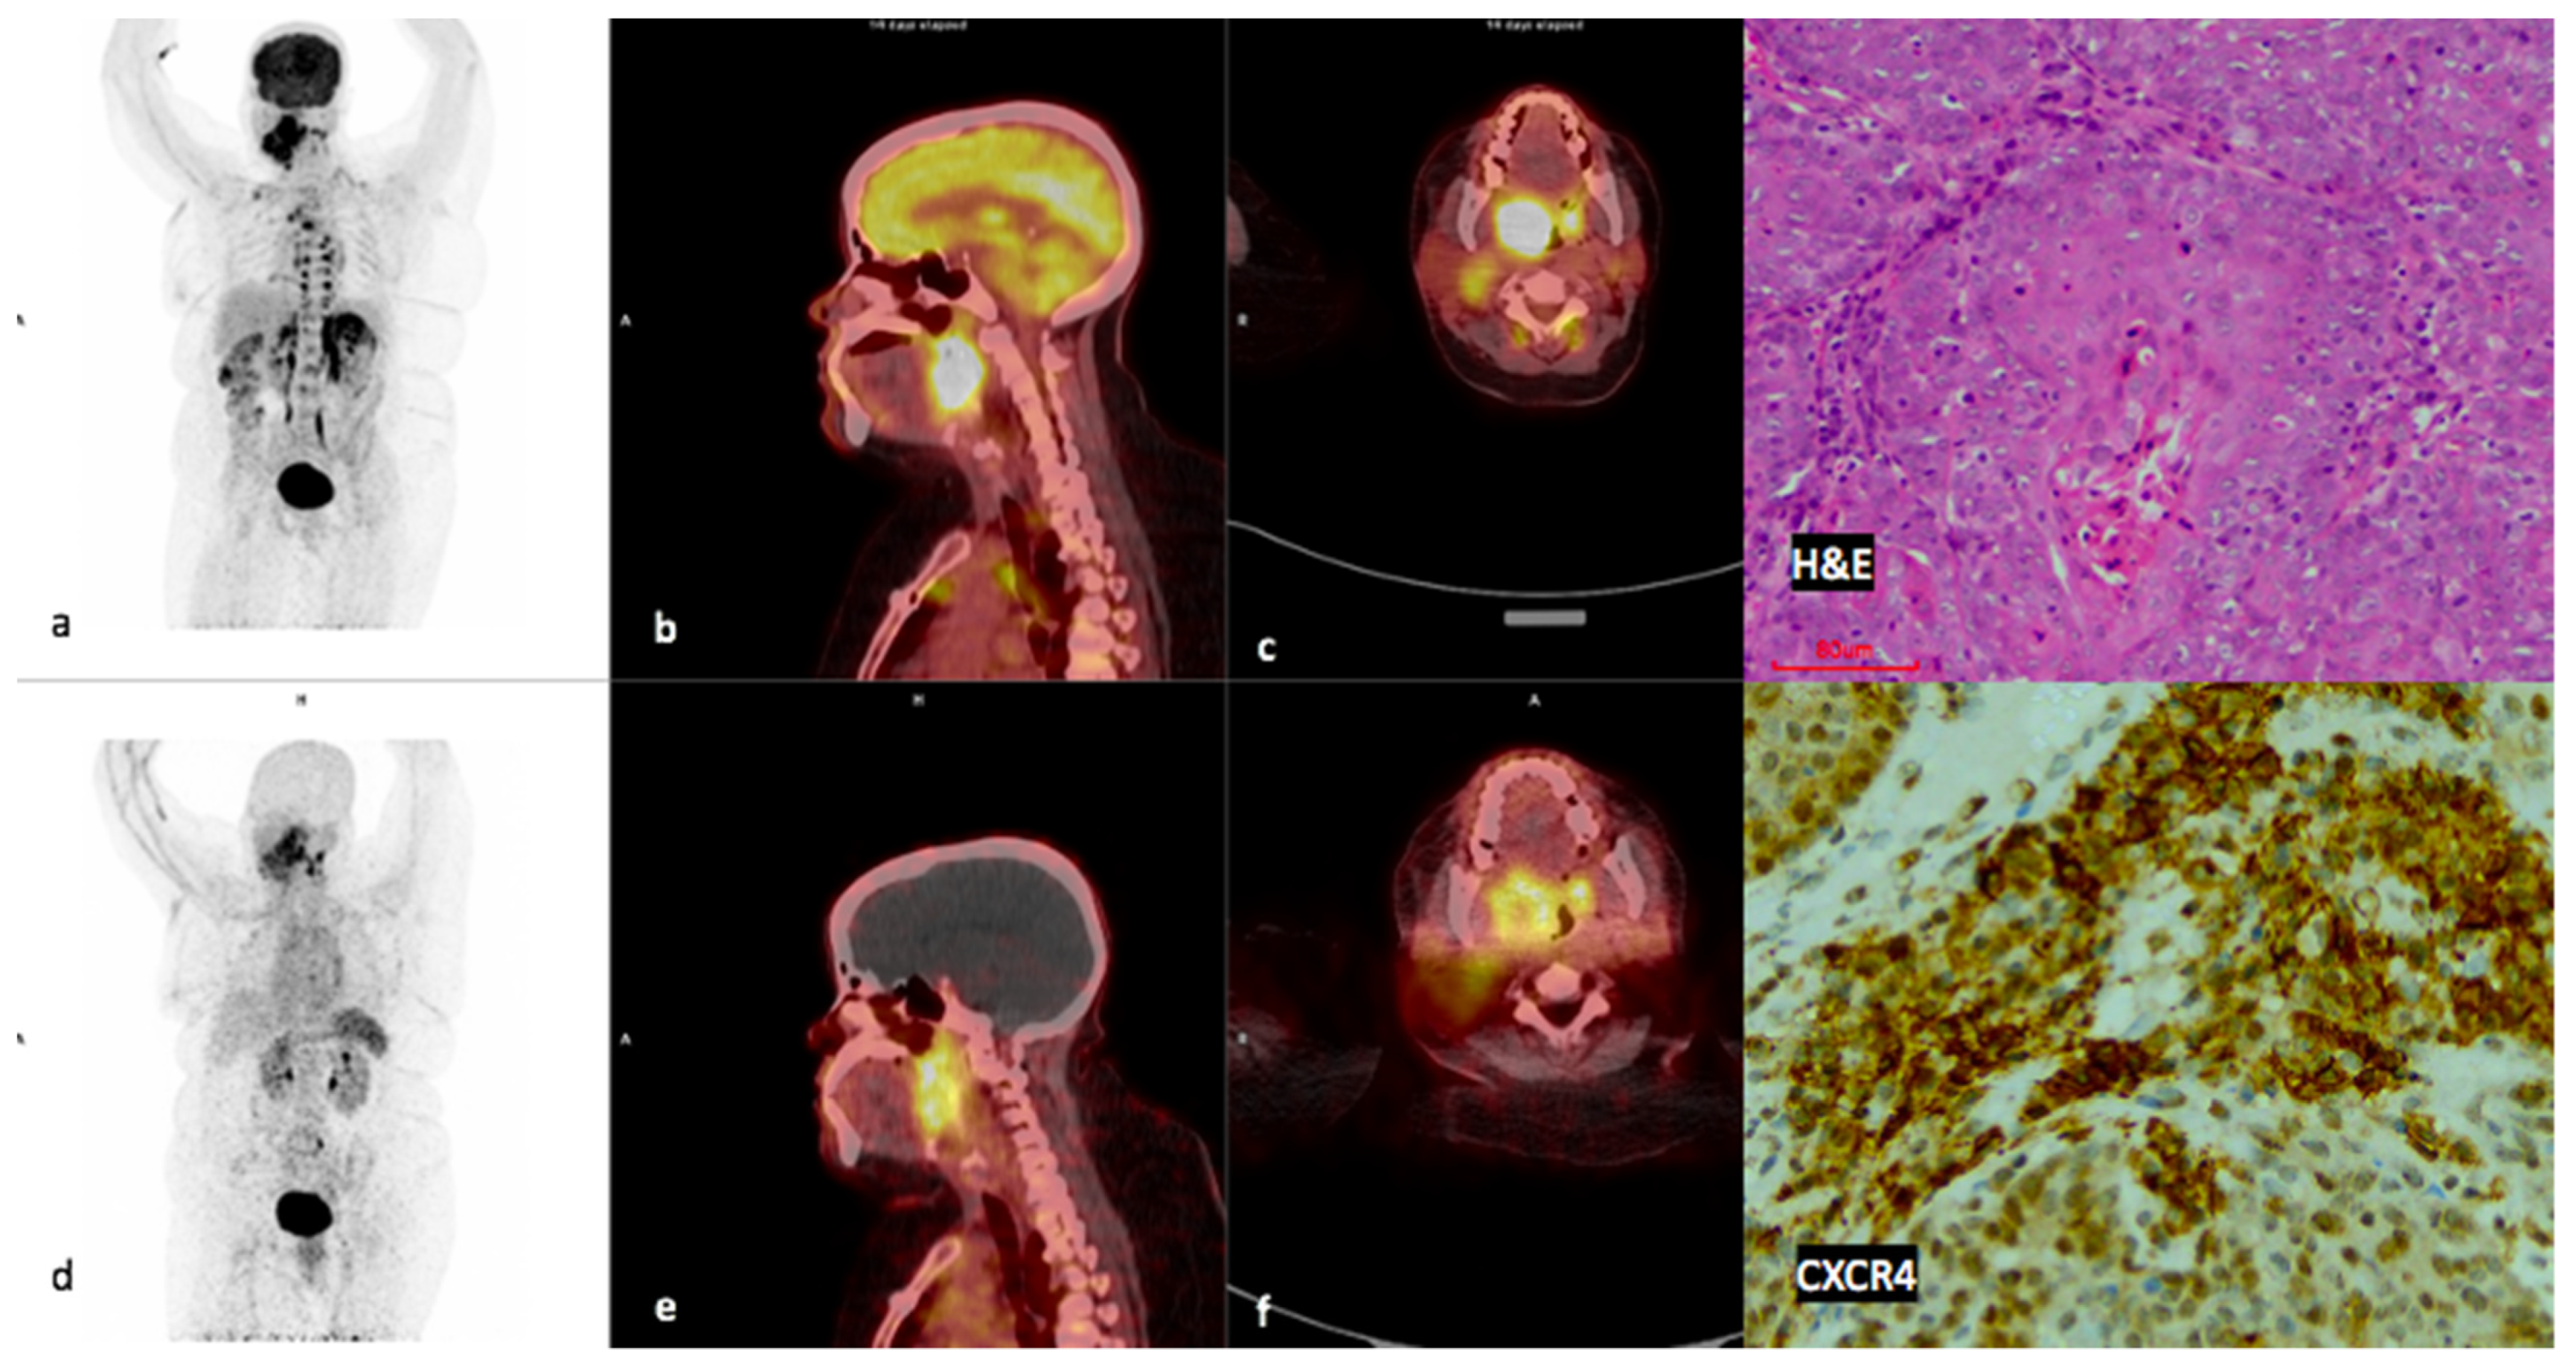

3.2. Comparison of FDG and 68Ga-Pentixafor

3.3. Visual Analysis

3.5. CXCR4 Immunohistochemistry (IHC)